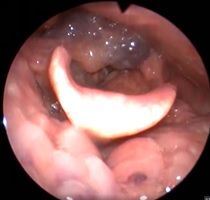

Клинический пример №5. Удаление полипа правой голосовой складки с использованием СО-2 лазера.

После операции, воспалительные проявления со стороны голосовой складки едва заметны.

Рис 5А Полип (отечный) правой голосовой складки. До операции.

Рис 5Б. Полип (отечный) правой голосовой складки. 1 день после операции.